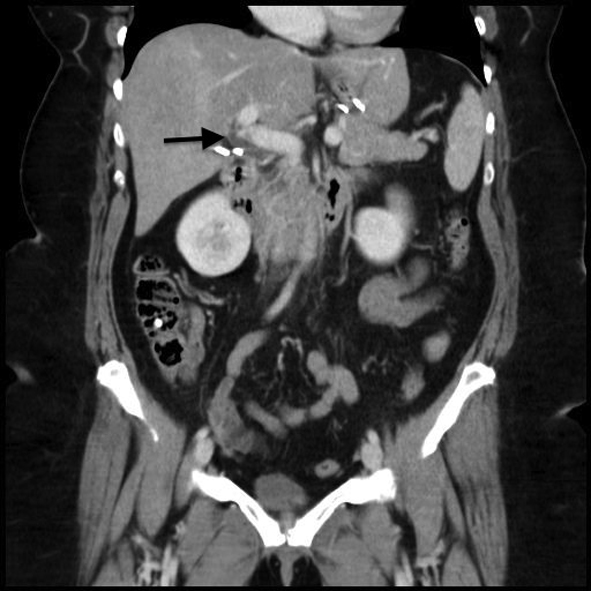

A 47-year-old woman underwent a laparoscopic sleeve gastrectomy for the treatment of obesity (BMI 43 kg/m2without comorbidity, decision validated upon multidisciplinary meeting). This patient had a treatment of an oral contraceptive. The laparoscopic sleeve gastrectomy was performed without difficulty, with an operating time of 60 min. The immediate postoperative course was uneventful and the hospitalization ended on the seventh postoperative day. The patient was hospitalized again in emergency, on the seventeenth postoperative day for epigastric pain and left hypochondrium that suddenly appeared 5 days before. It was a transfixing pain, associated with a low-grade fever (38 °C) and chills. The patient was neither tachycardic nor dysphagic nor dyspneic. The abdomen was painful with epigastric defense. Biology found hyperleukocytosis and an increased CRP. A CT scan with injected contrast product found inflammation of the cephalic peripancreatic fat, a portal thrombus at the junction of the superior mesenteric vein and spleno-mesenteric trunk, a permeable portal trunk and no sign of digestive distress (Fig. 2). Oral contraception was stopped; the thrombosis review was performed prior to the initiation of an anticoagulant treatment that combined a subcutaneously curative low molecular weight heparin and an antivitamin K treatment. The clinical result was favorable, with pain relief in 48 h. Feeding was resumed after 48 h. During the first postoperative month, the patient did not show any warning digestive sign, with a weight loss of 10 kg. The etiology was negative. An abdominopelvic CT scan control 1 month later showed the disappearance of the portal thrombus in the mesenteric vein, a free and permeable pedicle portal vein, but found thrombosis on the right portal branch (left portal branch permeable), with a right hyperdense liver lobe (Fig. 3). Treatment with vitamin K was maintained.

![]() Click for large image | Figure 2. Abdominal CT scan with injected on admission (case 2). Arrow: a portal thrombus at the junction of the superior mesenteric vein and spleno-mesenteric trunk. |